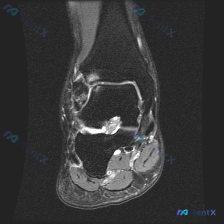

看到一个有意思的读片病例,问题是「这张影像存在什么发现,报告提示软骨异常」,整理了一下影像资料和分析思路,分享给大家。 病例基本影像信息 这是一张踝关节冠状位T2加权MRI,核心影像表现如下: 1. 距下关节间隙内可见明显异常高信号,提示关节积液或滑膜异常,高信号区域非常显著 2. 胫骨远端、距骨、...